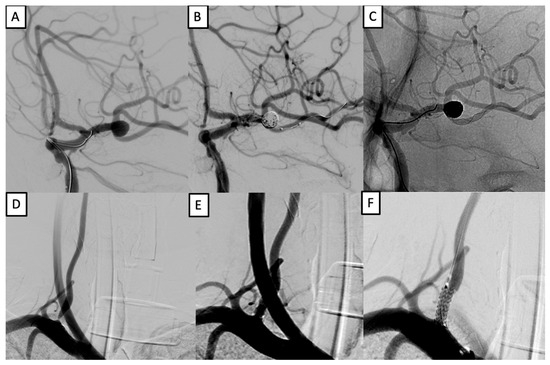

3.6. Case Examples